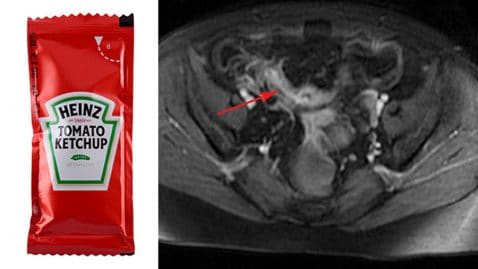

Attaqué par un requin alors qu’il se baignait Eugène Finney est l’heureux papa de deux magnifiques enfants, sa fille de […]